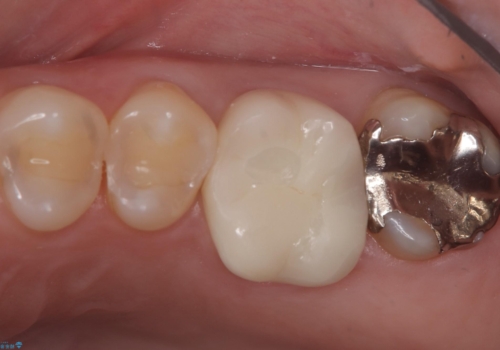

今後ホワイトニング行う予定のため、シェード明るめにしています。

・仮歯 10,000円(税抜き)

・オールセラミッククラウン(スタンダード) 110,000円(税抜き)